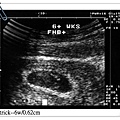

Patrick 六週時,身高才0.62公分...不到一公分比小蝦米還小~~